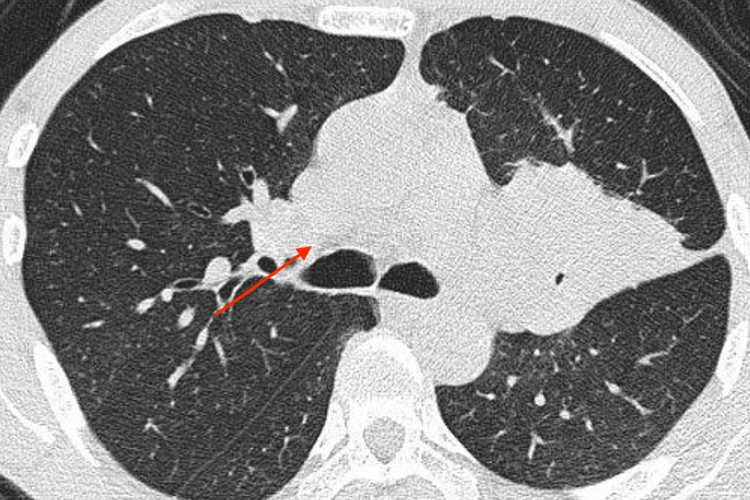

中央型

早期中央型肺癌可清晰显示支气管壁的不规则增厚、管腔狭窄或腔内结节等改变。中晚期中央型肺癌可清晰显示支气管腔内或壁内外肿块、管壁不规则和管腔呈“鼠尾状”狭窄或“锥形”、“杯口状”截断;阻塞性肺炎表现为受累支气管远侧肺组织实变,多为散在分布;发生肺不张时则表现肺叶或肺段的均匀性密度增高并伴有容积缩小。